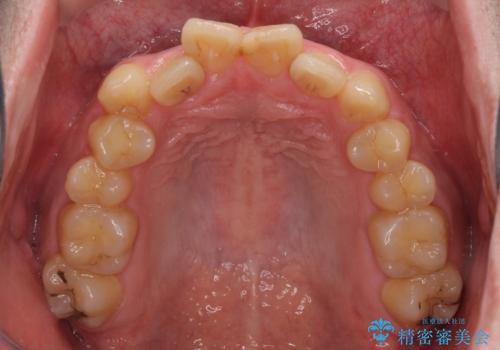

- 上下のデコボコと前歯のクロスバイトを改善したいとのことで来院された患者様です。

デコボコの程度は強かったのですが、口元の突出感はなかったため、非抜歯矯正としました。